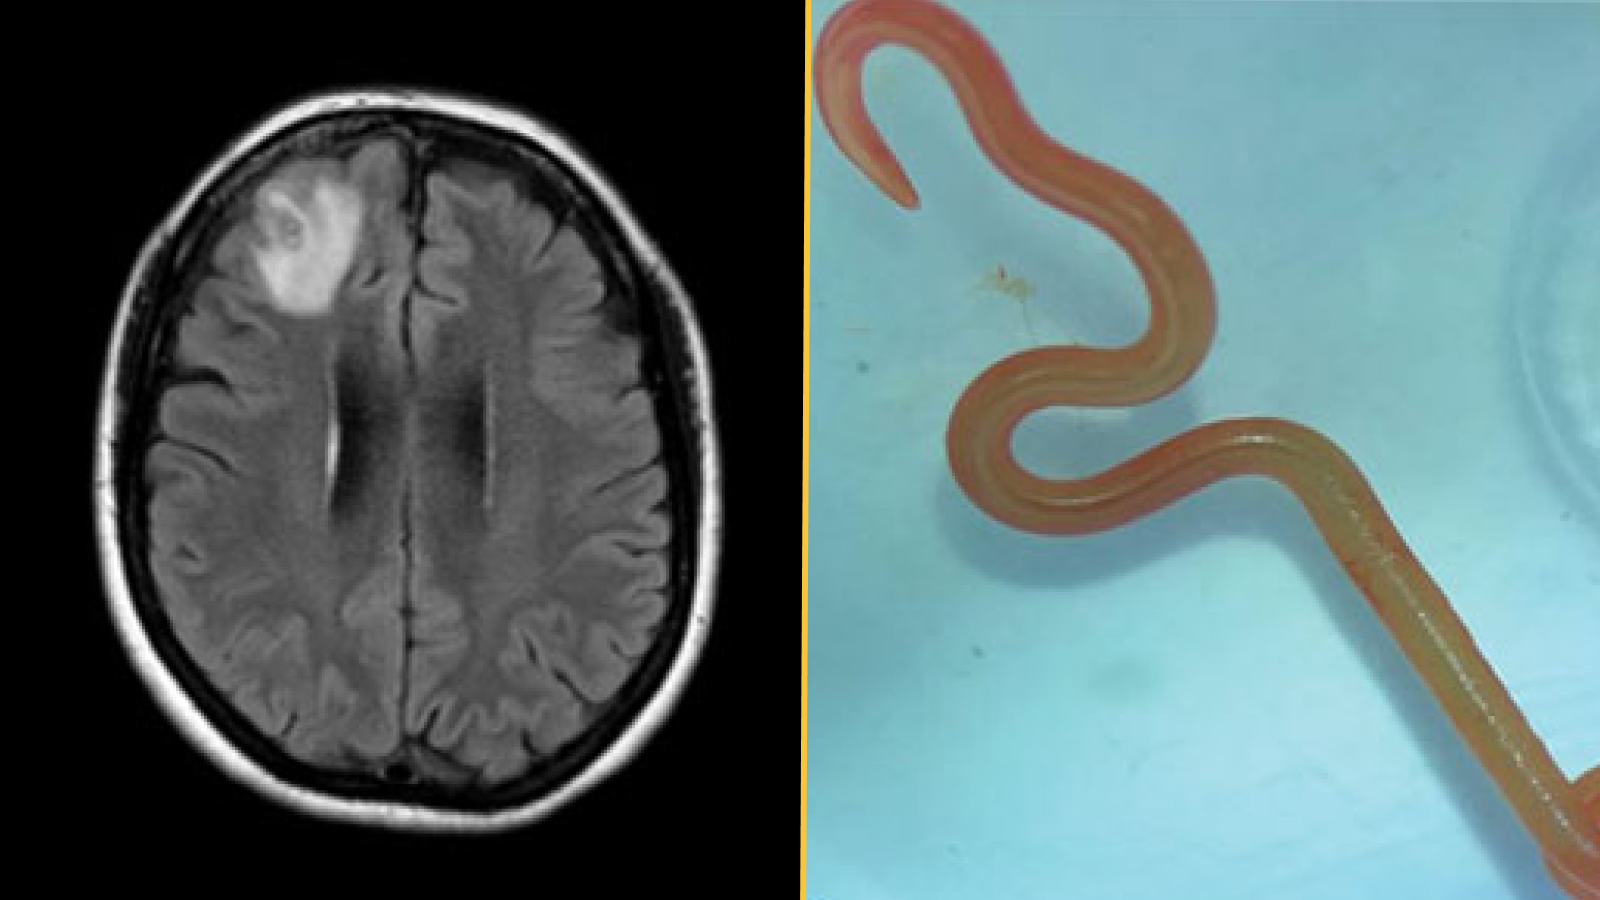

Que s’est-il passé ensuite : Une échographie pelvienne et une IRM ont révélé que même si la jeune fille avait un utérus, il lui manquait à la fois un col et un vagin. Les médecins ont ensuite confirmé leurs découvertes par une laparoscopie, une procédure au cours de laquelle un tube équipé d’une caméra est guidé dans le corps à travers une incision en trou de serrure. Ils n’ont vu ni col ni vagin, mais ils ont vu des ovaires et des trompes de Fallope sains, sans aucune preuve de endométriose.

Le diagnostic : L’absence totale de col à la naissance, connue sous le nom d’agénésie cervicale, est une forme d’atrésie cervicale, une maladie rare impliquant des malformations cervicales susceptibles d’affecter 1 naissance sur 100 000 à 1 naissance sur 80 000.

L’agénésie vaginale accompagne souvent l’atrésie cervicale. Une petite étude portant sur 18 femmes présentant un col manquant ou mal formé a révélé une agénésie vaginale chez environ 39% des patients. Le taux peut être beaucoup plus élevé chez les femmes présentant une agénésie cervicale complète, les données disponibles suggèrent.